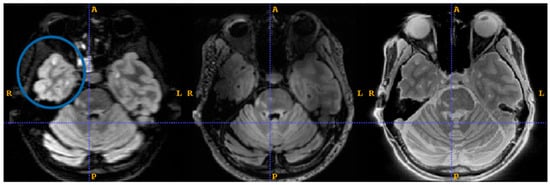

Figure 7 shows the boiled egg phantom (lower) and a small water-filled sphere (upper) scanned with MT-weighted Gradient-Echo images (left) and MT-weighted Silent (right). The images were acquired in register in the same session, as the added guidelines (gold arrows) show. The Gradient-Echo image shows good contrast between the white and the yolk of the egg. The Silent image suggests a greater level of structure and detail in the same egg at the same slice location.

Figure 7. MT-weighted scans of a boiled egg. MT-weighted Gradient Echo (left) SilentMT (right). Horizontal gold guide-lines have been added to aid visual comparison.

We cannot explain all the differences in the appearance of the Gradient-Echo and SilentMT images of the boiled egg, in particular the difference in apparent size of the egg; a more thorough investigation including B1 and B0 measurements might shed further light. More structural details were observed in the SilentMT image of the egg compared to the Gradient-Echo equivalent. Cooked egg is often used as a phantom for T2 [46] or MTR measurements [47]. The simplest explanation of this observation is that proteins in the egg decayed during the day it was left at room temperature, and these developed a greatly shortened T2, providing extra contrast which could not be detected by the Gradient-Echo image. The other possibility is that a Magnetisation Transfer effect could be taking place between two very short-T2 signal sources which is not observable with the MT-weighted Gradient Echo [20]. We do not currently have a method of measuring T2 values of less than 10 ms on our scanner, so we cannot verify either of these hypotheses at this time. Further investigations using more complex quantitative Magnetisation Transfer measures might be able to provide full explanations of all the features observed in the SilentMT egg image.